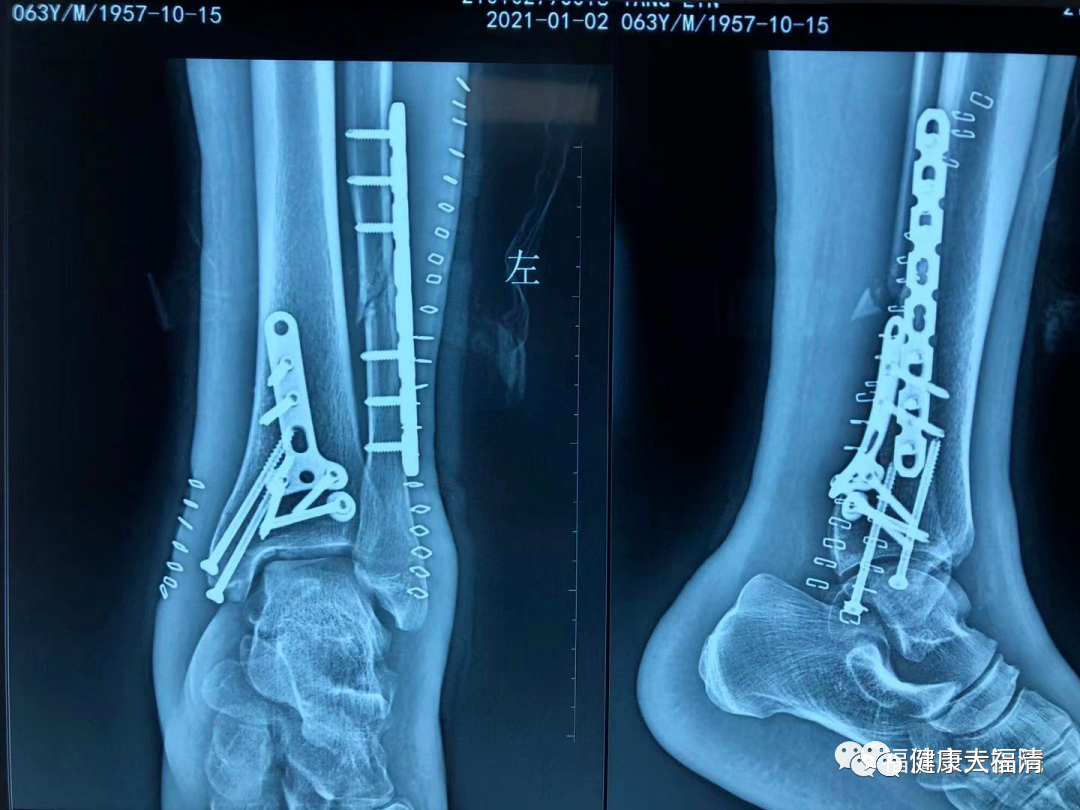

近日,市三医院接诊一位外地患者,该患者在工作时不慎被重物压伤,导致左踝关节肿胀畸形,皮肤出现血水泡。诊断为三踝骨折,属高能量损伤,软组织条件较差,术后容易出现皮瓣坏死、感染等相关风险。

经该院骨科一区副主任医师王秀华团队讨论后给予制定详细治疗方案,术中首次采用“钉皮机”缝合皮肤,手术顺利完成,术后切口愈合良好。